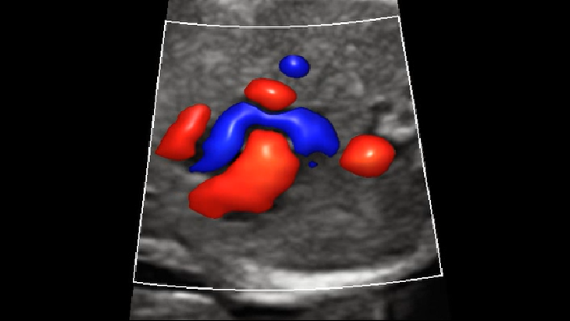

ImĂĄgenes clĂnicas